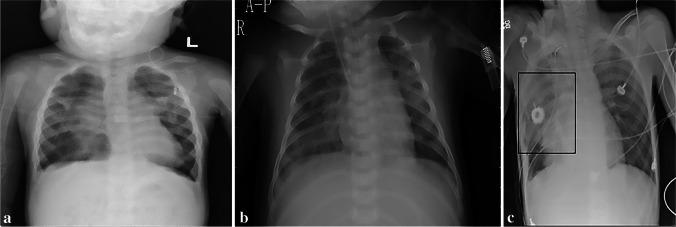

Most artificial intelligence (AI) studies have focused primarily on adult imaging, with less attention to the unique aspects of pediatric imaging. The objectives of this study were to (1) identify all publicly available pediatric datasets and determine their potential utility and limitations for pediatric AI studies and (2) systematically review the literature to assess the current state of AI in pediatric chest radiograph interpretation. We searched PubMed, Web of Science and Embase to retrieve all studies from 1990 to 2021 that assessed AI for pediatric chest radiograph interpretation and abstracted the datasets used to train and test AI algorithms, approaches and performance metrics. Of 29 publicly available chest radiograph datasets, 2 datasets included solely pediatric chest radiographs, and 7 datasets included pediatric and adult patients. We identified 55 articles that implemented an AI model to interpret pediatric chest radiographs or pediatric and adult chest radiographs. Classification of chest radiographs as pneumonia was the most common application of AI, evaluated in 65% of the studies. Although many studies report high diagnostic accuracy, most algorithms were not validated on external datasets. Most AI studies for pediatric chest radiograph interpretation have focused on a limited number of diseases, and progress is hindered by a lack of large-scale pediatric chest radiograph datasets.

大多数人工智能 (AI) 研究主要集中在成人成像上,而对儿科成像的独特方面关注较少。本研究的目的是:(1) 确定所有公开可用的儿科数据集,并确定其对儿科 AI 研究的潜在效用和局限性;(2) 系统地回顾文献,评估 AI 在儿科胸部 X 线片解读中的现状。我们在 PubMed、Web of Science 和 Embase 上搜索了从 1990 年到 2021 年评估 AI 用于儿科胸部 X 线片解读的所有研究,并提取了用于训练和测试 AI 算法、方法和性能指标的数据集。在 29 个公开的胸部 X 射线数据集,2 个数据集仅包括儿科胸部 X 射线,7 个数据集包括儿科和成人患者。我们确定了 55 篇文章,这些文章实施了 AI 模型来解读儿科胸部 X 射线或儿科和成人胸部 X 射线。AI 应用最广泛的是对胸部 X 射线进行肺炎分类,65%的研究都评估了这一应用。尽管许多研究报告了高诊断准确性,但大多数算法并未在外部数据集上进行验证。大多数用于儿科胸部 X 射线解读的 AI 研究都集中在少数几种疾病上,由于缺乏大规模的儿科胸部 X 射线数据集,进展受到阻碍。